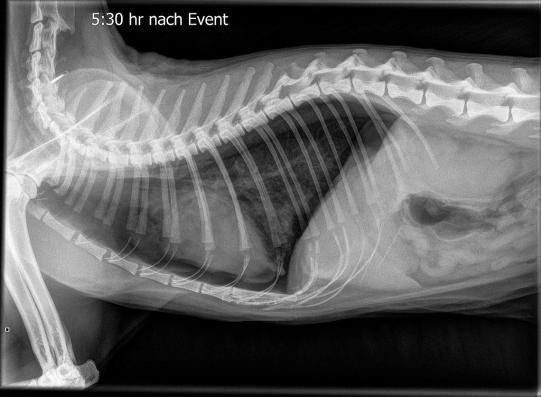

Um die Luft zwischen Lunge und Brustkorb zu entfernen, wird bei Muffin umgehend auf beiden Brustseiten eine Brusthöhlenpunktion durchgeführt. Kurz darauf atmet die Katze deutlich besser; ein weiteres Röntgenbild knapp 6 Stunden nach Eintreten des Notfalls zeigt, dass sich der Pneumothorax glücklicherweise nicht erneut verstärkt hat. Auf eine weitere Punktion kann deshalb verzichtet werden.